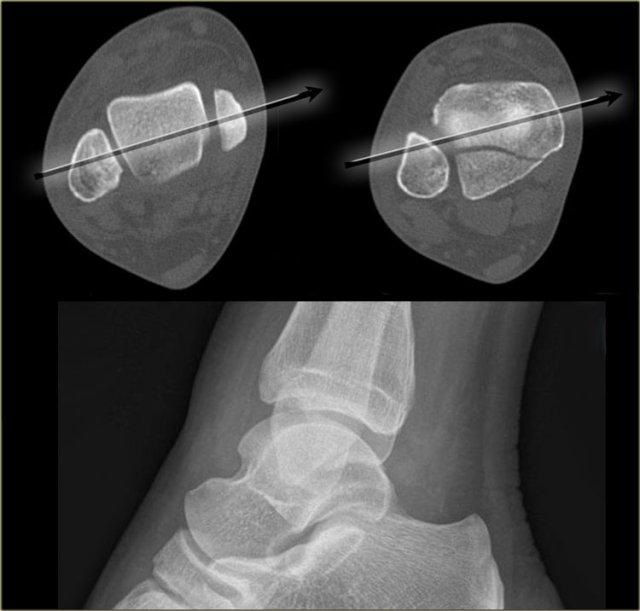

Good positioning of the lateral view - Tertius fracture Good positioning of the lateral view - Tertius fracture

On a well positioned lateral view the tertius fracture is obvious (red arrow).

This was the only fracture that was seen on the x-rays of the ankle and this patient turned out to have an unstable Weber-C fracture and went for surgery.

The x-ray beam has to be centered on the malleoli.

Notice the exorotation of the foot for a proper lateral view.